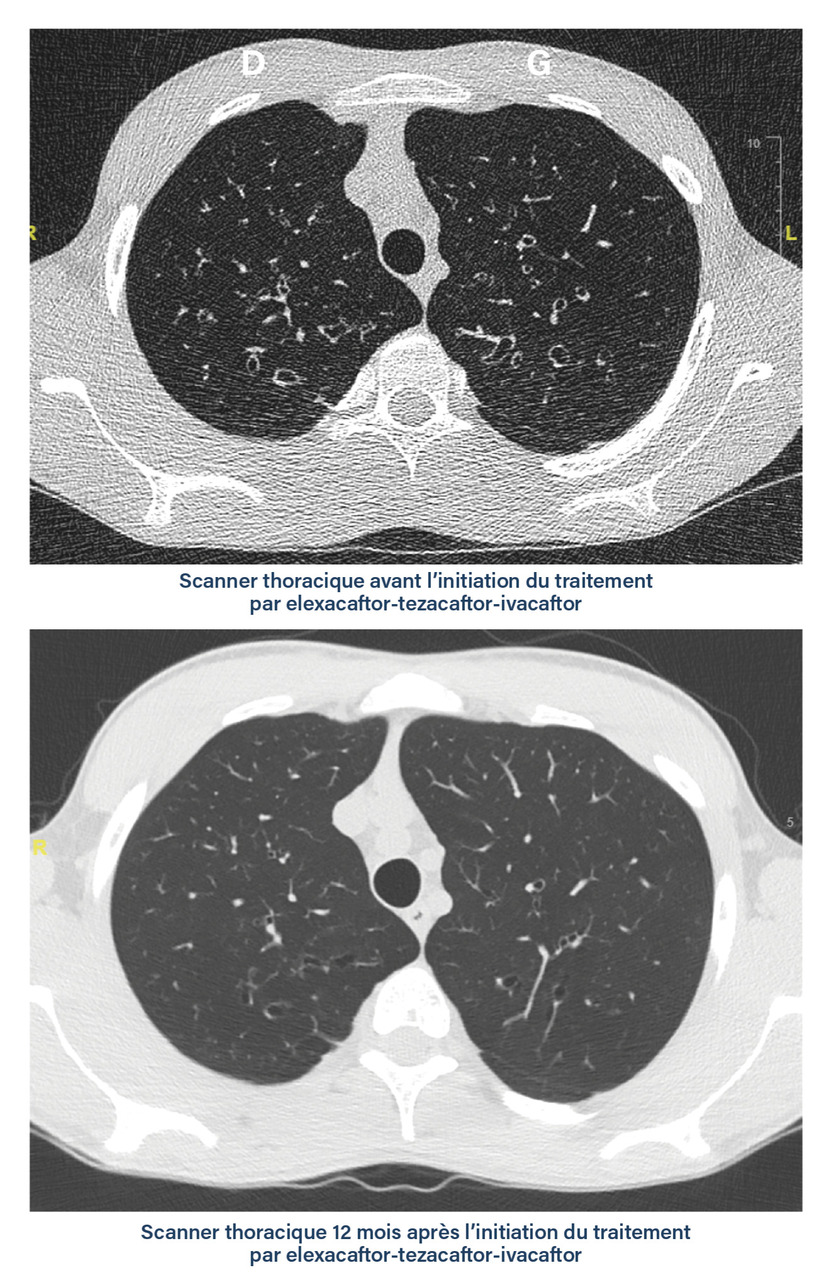

Quelques situations cliniques aiguës peuvent nécessiter la réalisation d’examens d’imagerie thoracique en urgence  : c’est le cas notamment des douleurs thoraciques aiguës et des hémoptysies. Le diagnostic d’exacerbation respiratoire ne nécessite le plus souvent pas le recours à des examens radiologiques, mais la non-réponse au traitement bien conduit peut justifier de réaliser une radiographie du thorax ou un scanner thoracique pour rechercher une explication telle que l’aspergillose bronchopulmonaire allergique. Dans ce cas, des signes radiologiques spécifiques peuvent être mis en évidence tels que l’inversion de contraste des impactions mucoïdes (fig. 2).6